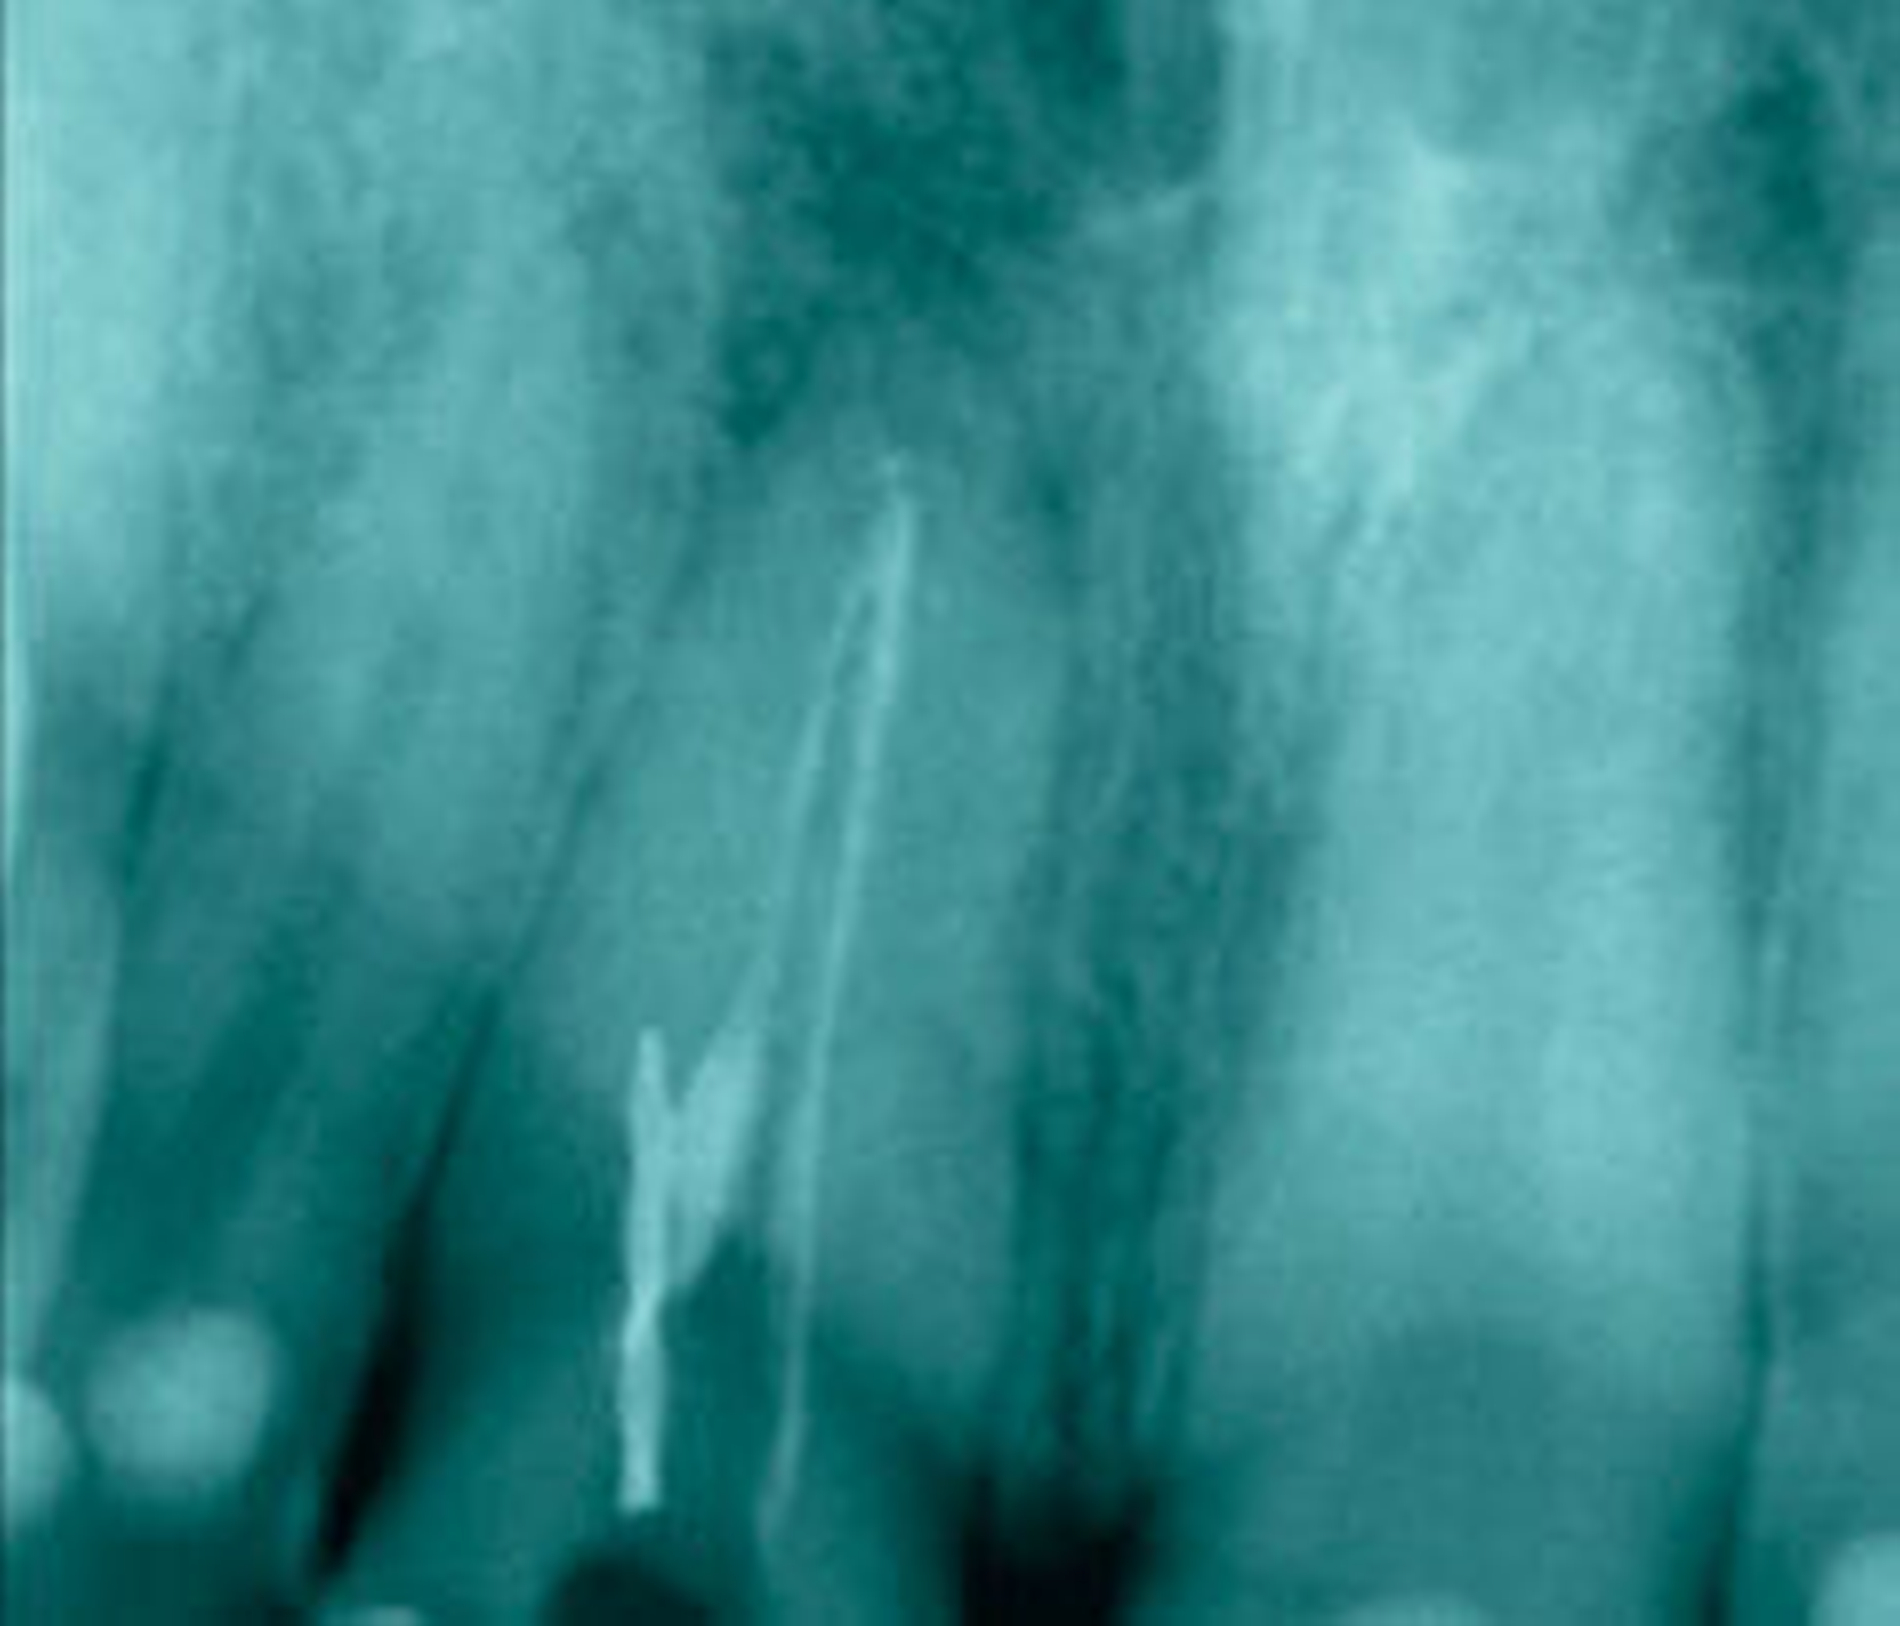

(Fall 3) Sowohl klinisch als auch röntgenologisch ließ sich bei der Patientin ein sanierungsbedürftiges Gebiss feststellen. Nach der Anfertigung einer Panoramaschichtaufnahme wurde bereits ein Instrumentenfragment im Zahn 11 vermutet (Abbildung 1). Der anschließend angefertigte Zahnfilm bestätigte diese Vermutung (Abbildung 2). Ungewöhnlich ist die Lage des Instruments abseits des Hauptkanals. Aufgrund dessen muss von einer fehlerhaften Anwendung der genutzten Feile ausgegangen werden.

Der vergleichsweise große Durchmesser des frakturierten Instruments lässt auf eine maschinelle Nickel-Titan-Feile schließen. Aufdem angefertigten Röntgenbild ist neben dem frakturierten Instrument auch röntgenopakes Material innerhalb des Wurzelkanals zu erkennen. Es handelt sich aller Wahrscheinlichkeit nach um Reste alten Wurzelfüllmaterials, das im Zuge einer begonnenen Revisionsbehandlung durch den ehemaligen Hauszahnarzt im Wurzelkanalsystem verblieben ist. Der Zahn war zum Zeitpunkt der Erstvorstellung seit über zwei Monaten trepaniert und unverschlossen. Aufgrund des geringen Schwierigkeitsgrades und der großen Aussicht auf Erfolg kam nur der Versuch der Fragmententfernung in Betracht.